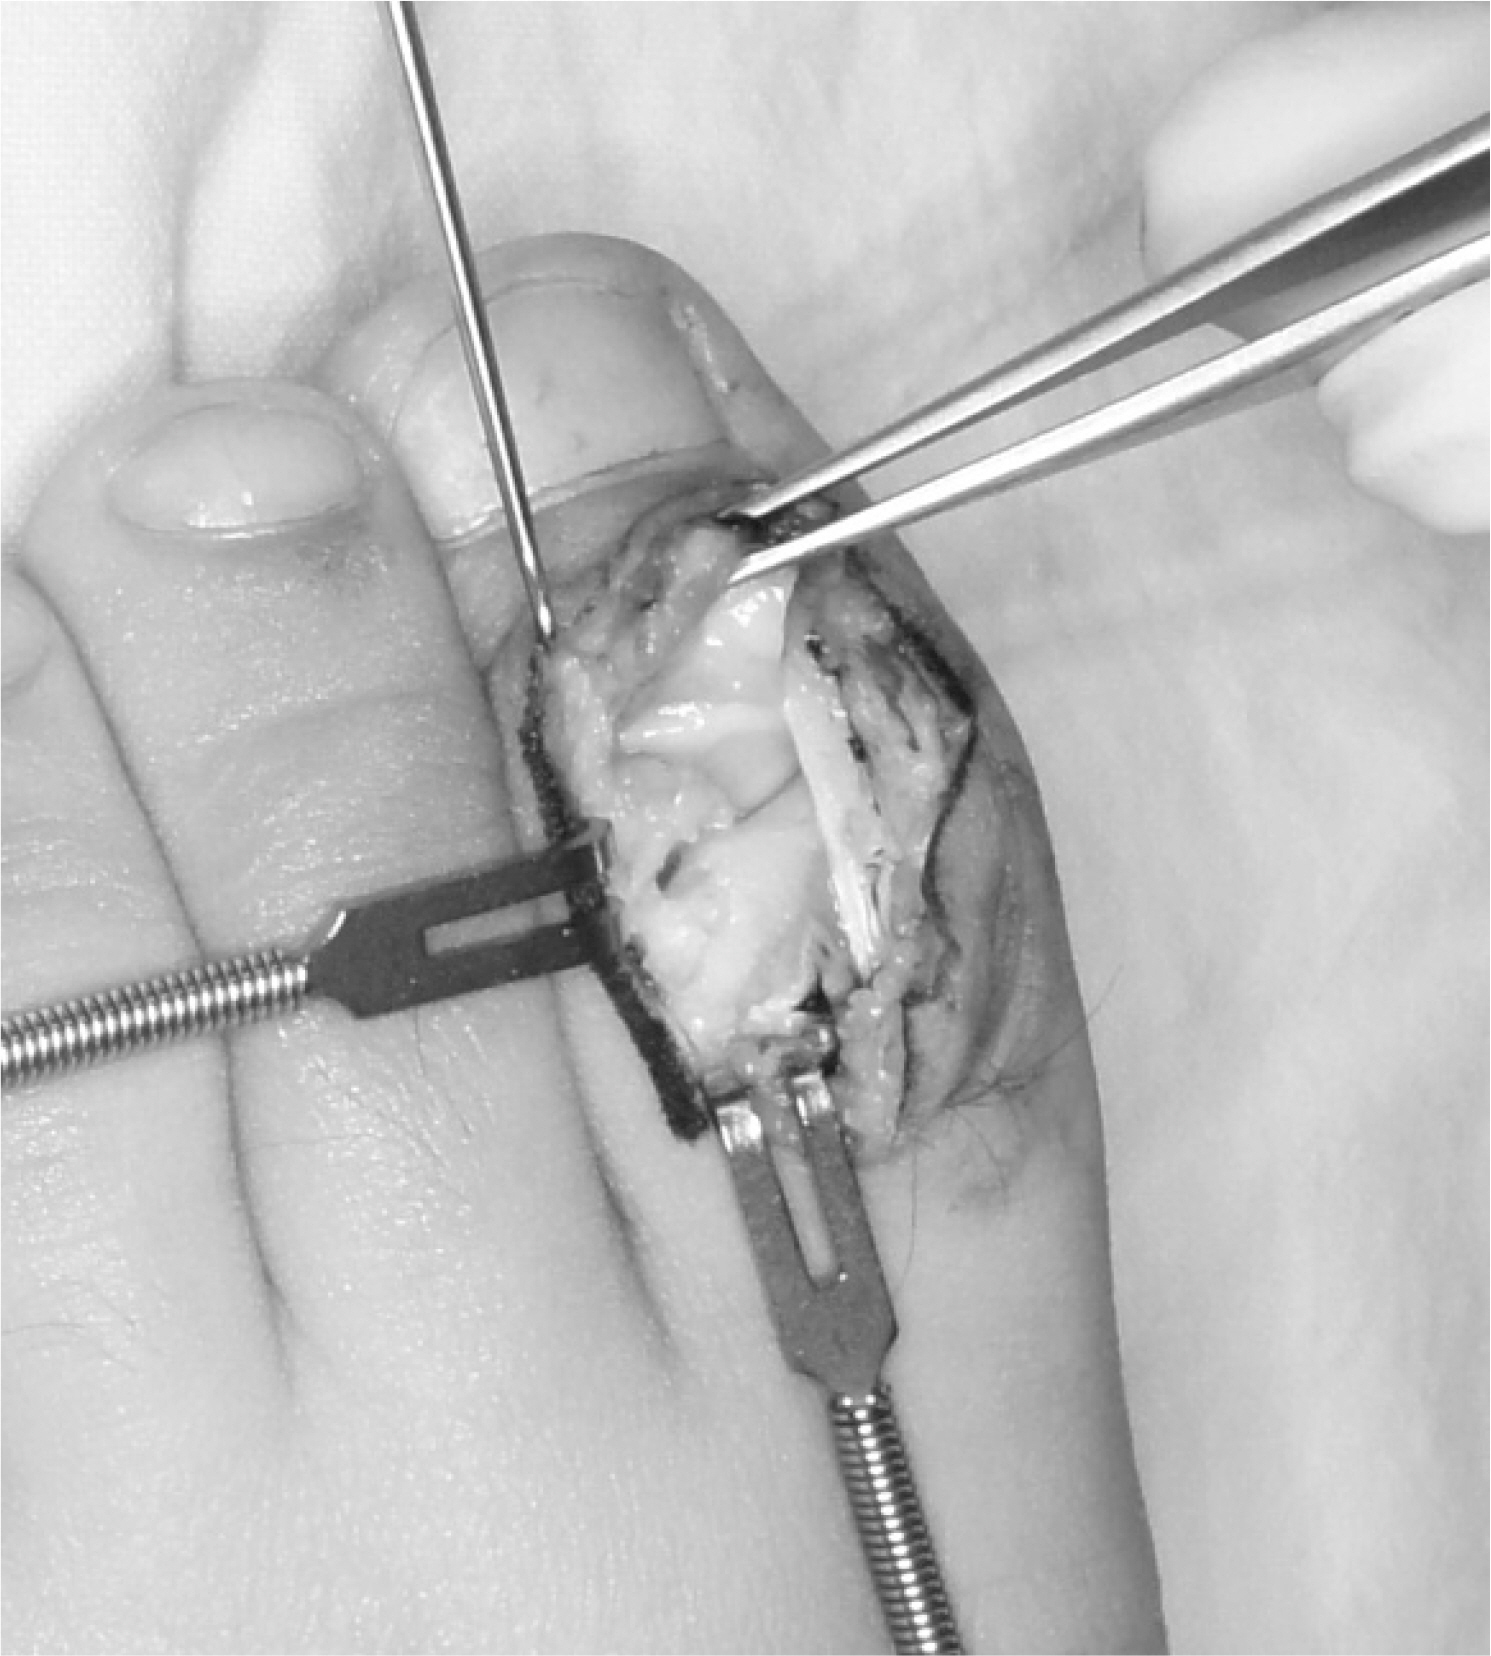

Fig. 2.

(A) Rotation of the osteochondral fragment (arrow). (B) Entrapment of the periosteum in the fracture site (arrowhead).

The joint surface was exposed through the dorsal approach. Sclerotic margin of the fracture site was observed.

A K-wire was inserted into the fragment and retracted from the opposite side to avoid unwanted traction when removing the wire.